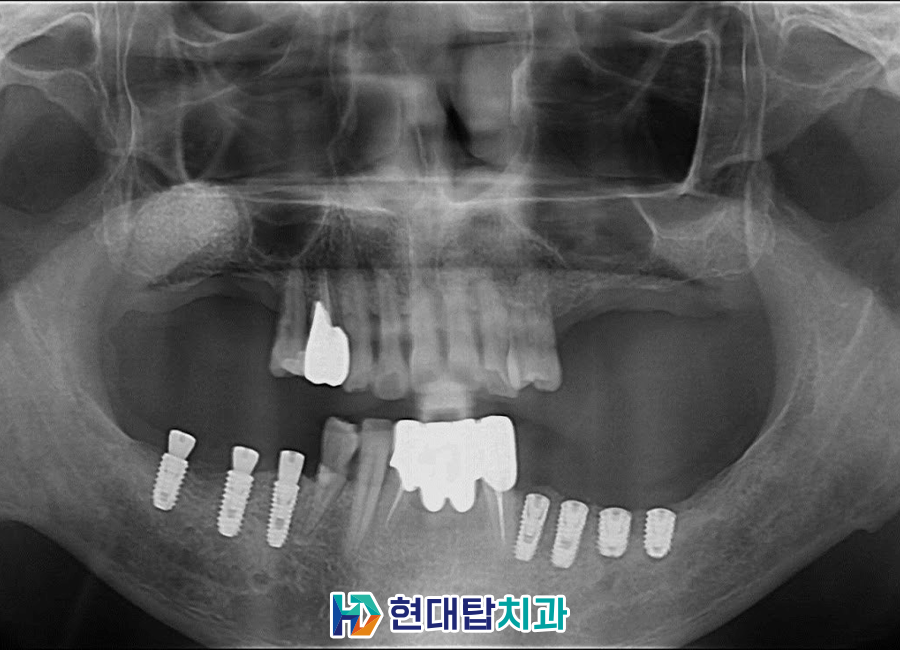

오른쪽 위쪽은 오랜 기간

치아가 상실된 상태로 지내시다 보니

잇몸뼈가 많이 부족하여

상악동거상술을 먼저 시행하였습니다.

뼈이식을 한 후에는 잇몸뼈가

단단하게 굳을 수 있도록 충분한

기간을 기다려주어야 하기 때문에

아래쪽 임플란트를 먼저 식립한 후

앞니 보철치료까지 완료하였습니다.

단단하게 뼈가 만들어진 후

위쪽 임플란트를 식립한 모습입니다.

아래쪽은 중간 연결기둥을 체결하였고